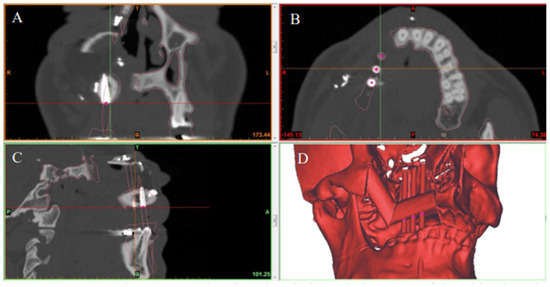

The primary outcome of this study was the accuracy of the postoperative implant positions as compared to the SDS plan. Each patient had a high-resolution helical CT scan of the facial bones using either a Somatom Sensation (Siemens, Germany) or a GE VCT (GE Healthcare, Waukesha, WI) 64-slice CT select scanner via a 0.625 mm collimation with a 25.0 cm field of view and 0 degree gantry tilt. All patients had postoperative CT scans of their facial bones 6–12 months after the Stage II procedure.

2.6. Data Analysis

The preoperative digital plan, referred to as “planned”, and the scans of the postoperative results, referred to as “actual”, were used for our analysis. Digitally placed spheres (1 mm diameter) were manually positioned in the geometric center of the planned and actual implant positions along the occlusal surface of the fibula. The spheres defined the reference point for measuring implant position. The X, Y, and Z coordinates of each planned and actual implant position were obtained (Figure 5 and Figure 6). The difference in position of the dental implants between the preoperative planned and postoperative actual CT scans was calculated in millimeters.

Figure 6. Postoperative CT scan showing the actual position of dental implants in the reconstructed jaw in the (A) coronal, (B) axial, and (C) sagittal planes. (D) 3D model showing final jaw reconstruction with implants in their actual position.